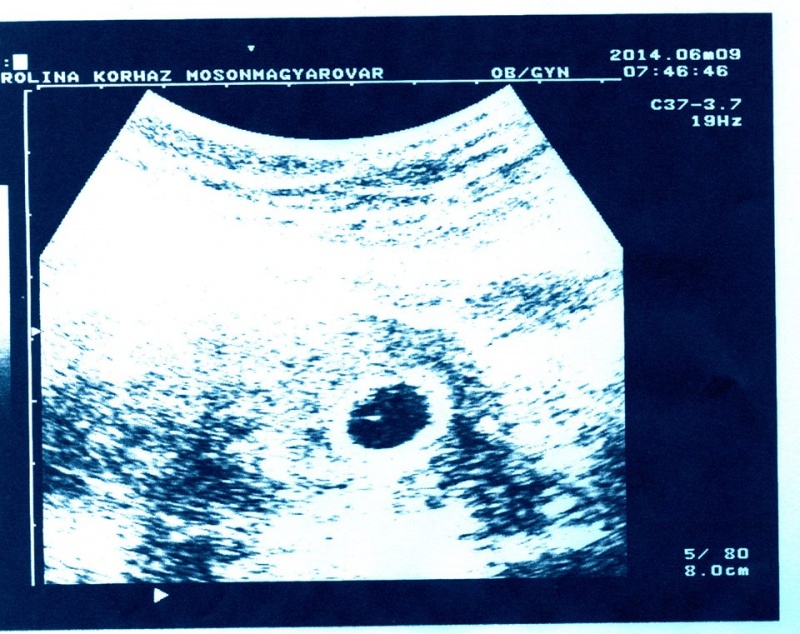

![]() Kislányod hatalmas! Nekünk a kisfiunk a 32. héten volt 2070 g és mondták, hogy jajj, nagyon nagy baba lesz... És neked nem is volt magas a cukrod?! (Vagy csaltál és sétafikáltál a cukorlötty után?) Totál életképes méret. De biztosan bennmarad még jóideig...

Kislányod hatalmas! Nekünk a kisfiunk a 32. héten volt 2070 g és mondták, hogy jajj, nagyon nagy baba lesz... És neked nem is volt magas a cukrod?! (Vagy csaltál és sétafikáltál a cukorlötty után?) Totál életképes méret. De biztosan bennmarad még jóideig...